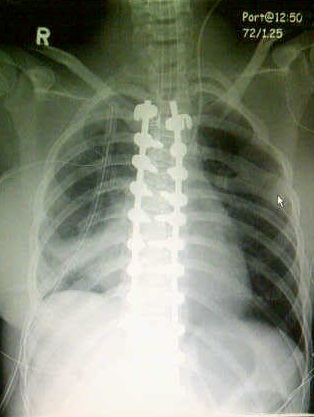

This X-ray picture is post-surgery, she now has a rod fused to either side of her spine in the thoracic region and many screws (I think 11 a side, total 22) to keep the rods in place to her spine. It sounds really harsh, and it is, and honestly I’m surprised in a week after surgery she doesn’t have a lot of pain, part of that is that she does have a high pain tolerance but I also think it is a good indication of how much pain and/or discomfort she was in enduring prior to the surgery.

I’m hoping these X-ray picture attachments are viewable for everyone, this one is a month before the surgery, it is a front view, her curve was on the right side of her torso on her back so her rib cage on the right side looked almost like it was winged out. A curve of this degree (92%) and even further puts a lot of pressure on many different areas of the body, my daughter is special needs and non-verbal so knowing exactly how it was affecting her was not precise but I did notice that her oxygen capacity was definitely compromised, she tired just from walking across the room. From December of last year to April of this year she had lost 25 pounds because she just wasn’t eating her usual, again hard to know exactly how strongly it was affecting her but the X-ray also showed that her spine was pushing inward as well which meant her stomach capacity may be compromised, hence the weight loss and lack of regular feed.